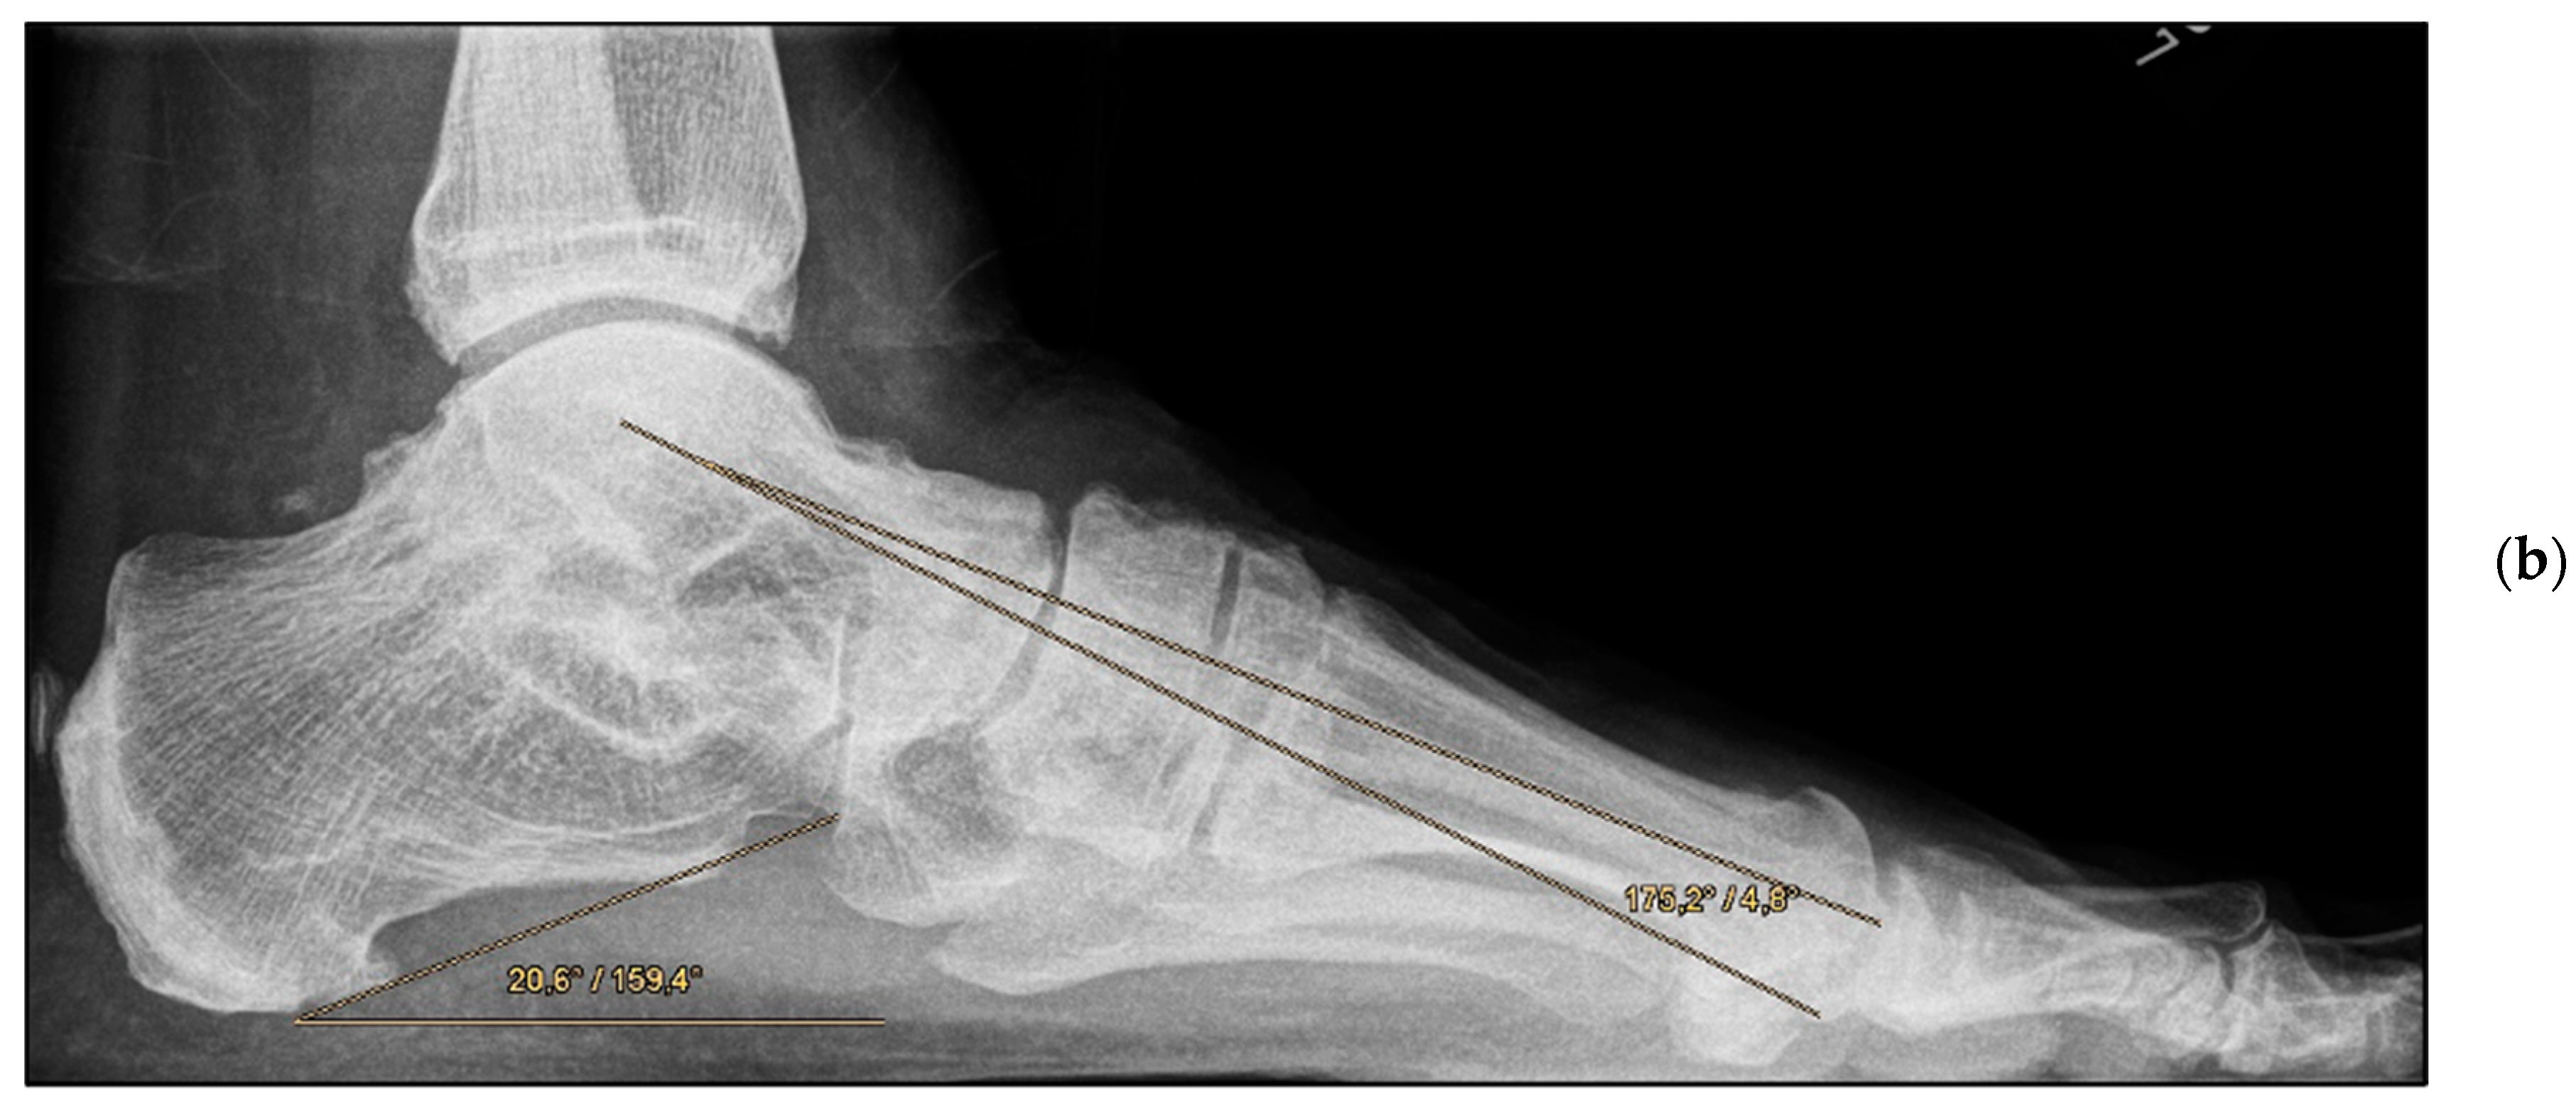

Figure 3.

Pre- and post-operative radiographic findings of combined talonavicular arthrodesis and calcaneal displacement osteotomy, left foot. (a) Lateral view pre-operative, (b) lateral view post-operative.

Medial calcaneal displacement osteotomy and talonavicular arthrodesis (Group A). In the first step, a V-shaped osteotomy was performed via an oblique approach to the lateral calcaneus with medial displacement of the back portion of the calcaneus. Osteotomy was performed using either an oscillating bone saw or bone chisel. Depending on the extent of the deformity, a medial displacement of approximately 8–10 mm was considered optimal. Fixation was achieved by means of two percutaneously inserted lag screws with diameters of 4.0–6.5 mm. The second step was talonavicular arthrodesis via a dorsal approach, usually with interposition of an iliac crest bone graft. Fixation was performed using two or three screws with diameters of 4 mm or a combination of screws and Nitinol compression implants (Figure 2a,b and Figure 3a,b).